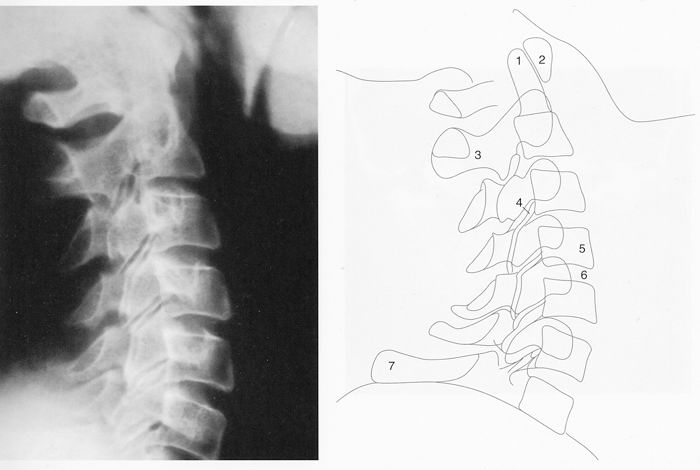

6. Disque intervétébralRachis cervical : radiographie, incidence de profil

1. Dent de l'Axis

2. Arc atérieur de l'Atlas

3. Procéssus épineux de l'Axis

4. Articulation zygapophysaire

5. Corps vertébral

6. Disque intervertébral

7. Processus épineux